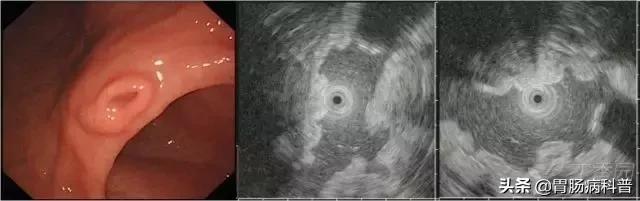

图 2胃神经内分泌瘤。

白光下胃体下前壁可见扁平黏膜下隆起,表面可见血管显露,EUS 下黏膜深层-黏膜下层可见低回声病变